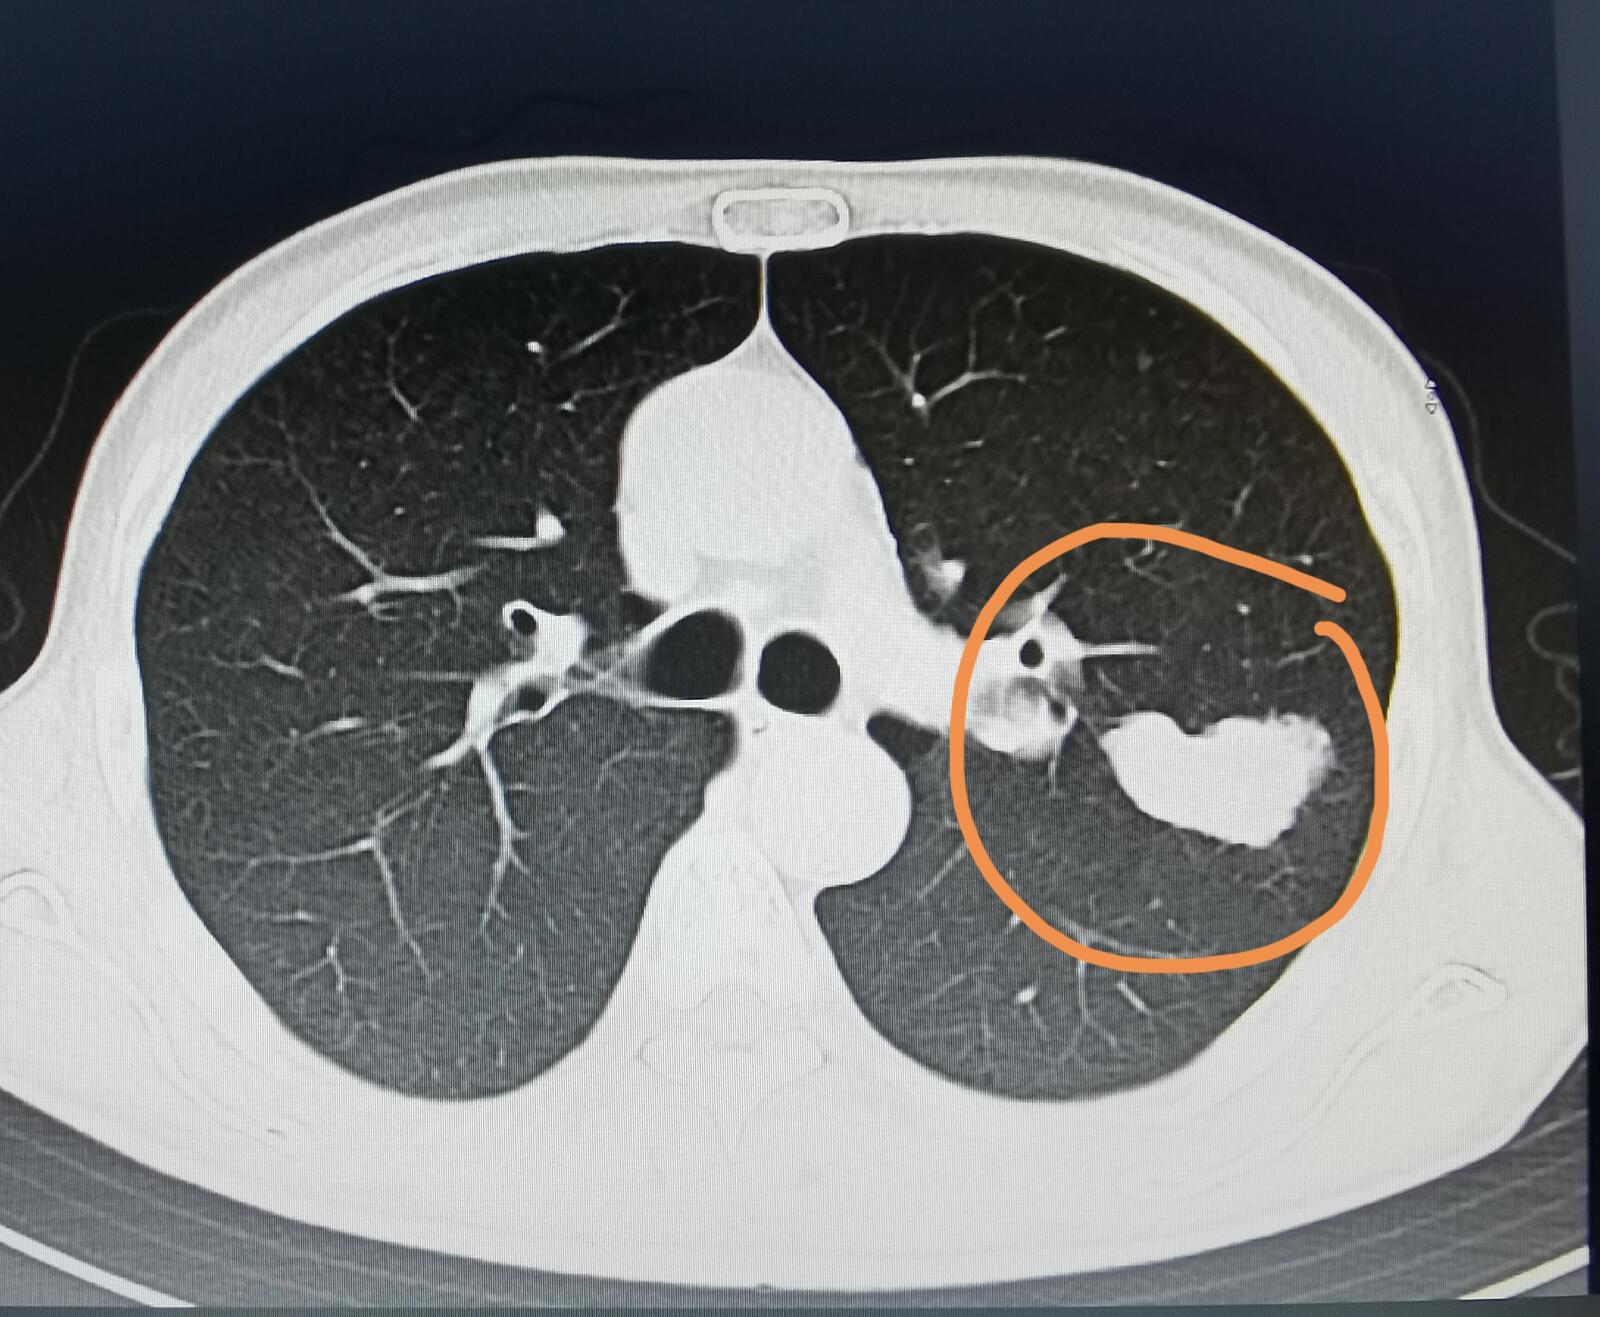

有一位家住河北省57岁的男士,近两个月来出现了上腹部疼痛,这种疼痛比较轻微,可以忍受,不是那种特别剧烈的,应该叫做隐隐作痛。刚开始的时候,他以为是胃口的问题,但后来这种感觉一直存在,他到我们医院来检查,发现了胰腺有一个占位,考虑是胰腺癌。同时一侧肾上腺和脾脏里面也都有占位,有可能是胰腺癌的转移。他在我们医院还做了一个胸部CT,结果发现了在左下肺也有一个占位。

他的儿子想知道左肺这个占位和胰腺癌有没有关系?我仔细阅读他的片子,觉得肺部这个占位恶性的可能性非常大,但考虑原发性肺癌,不太考虑胰腺癌的肺部转移。当然,最终还要以病理报告来决定到底是什么病。从他儿子那里我知道,这位患者抽了很长时间的烟,但之前从来没有做过体检,这还是他第一次做胸部CT和腹部的检查。